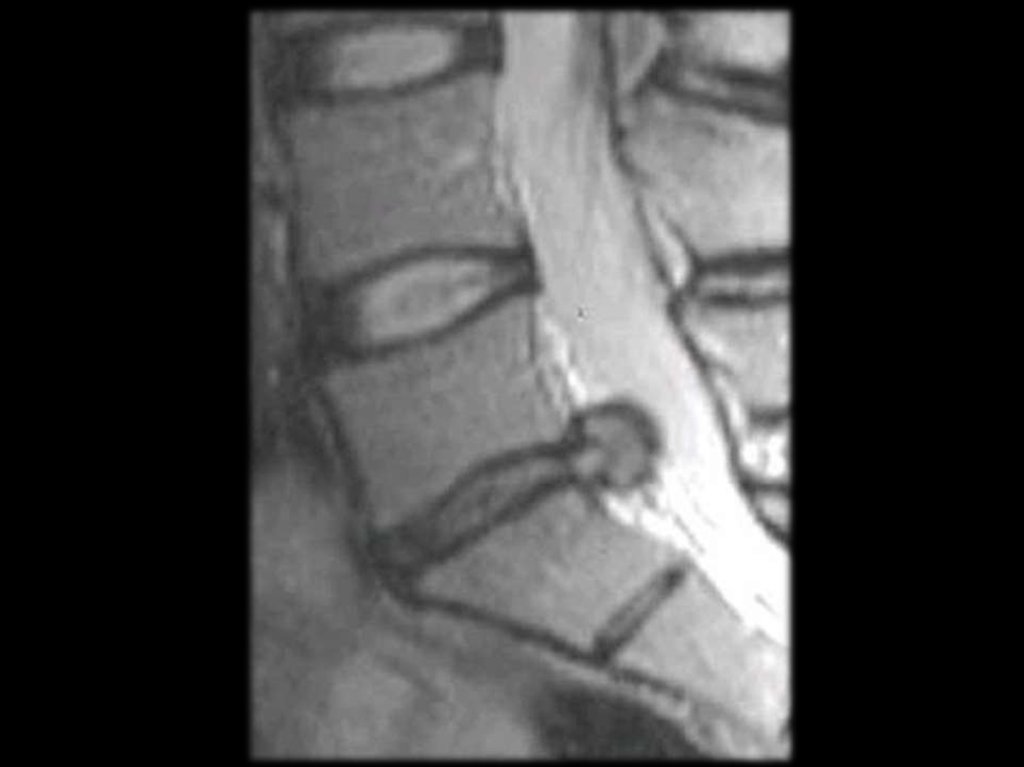

Грыжа диска

Грыжа диска – выпячивание диска за края линии,

соединяющей тела позвонков более 3 мм.

Выпячивание

диска

считается

клинически

значимым, если выпячивание занимает больше

25%

переднезаднего

размера

диаметра

позвоночного канала (≈ 10 мм).

Вызывает смещение задней продольной связки,

компрессию и раздражение спинномозговых

корешков.